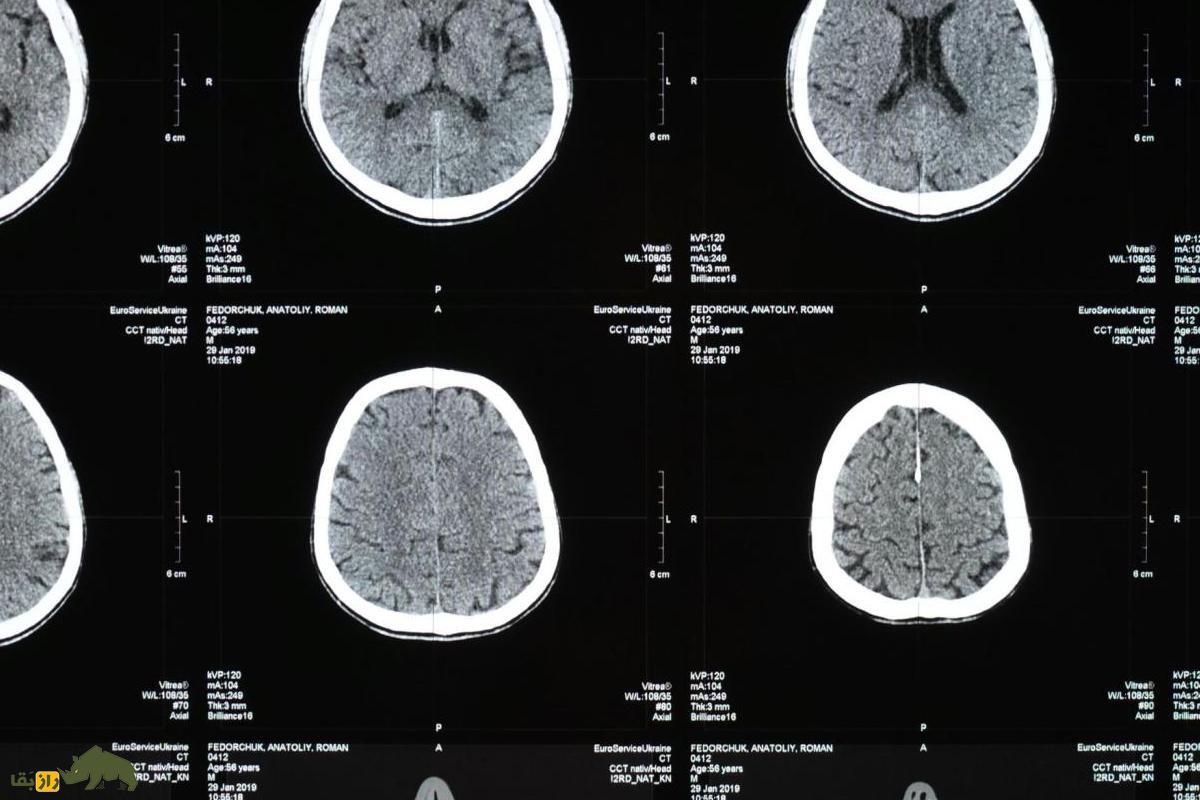

بیمار در اواخر ژانویه ۲۰۲۱ در بیمارستان بستری شد و سپس اسکن‌های مغزی نشان داد که یک ضایعه در مغز او وجود دارد. پس از آن در ژوئن ۲۰۲۲ در اتاق عمل مشخص شد که وجود یک کرم زنده سبب نشانه‌های بیماری این زن بوده است.